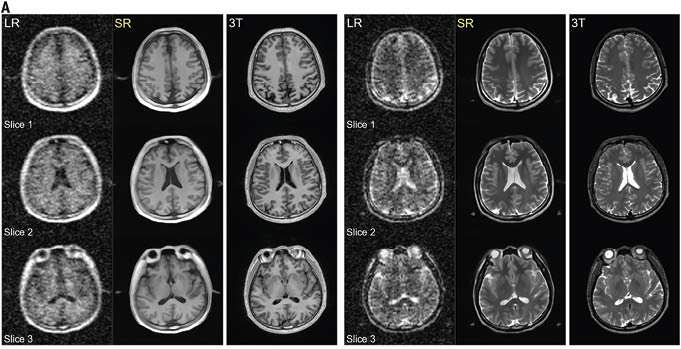

(A) O modelo de predição da idade cerebral é construído alavancando o treinamento do algoritmo LightGBM em 1.425 fenótipos derivados de imagem (IDPs) de ressonância magnética cerebral ponderada em T1 e idade cronológica. As características inicialmente passam por uma classificação de importância de características baseada em árvore, onde as 50 principais características importantes são selecionadas. Em seguida, a distância supervisionada entre cada característica é calculada e então submetida a agrupamento de hierarquia para identificar grupos de características redundantes. Após remover a redundância, interpretamos visualmente o subconjunto final selecionado de características usando a técnica SHAP. Para lidar com o viés, a idade cerebral prevista foi corrigida pelo método linear. (B) Primeiro, investigamos as correlações entre AP e BAG medidos objetivamente usando modelos não lineares e lineares. Em seguida, para obter insights sobre AP e estruturas cerebrais, investigamos as correlações entre AP e 1.425 IDPs usando modelos não lineares e lineares. (C) Para verificar se AP e saúde cerebral foram mediadas por BAG, conduzimos uma análise de mediação. Função cognitiva e distúrbios cerebrais foram selecionados como desfechos de interesse para a saúde cerebral. LightGBM, Máquina de Intensificação de Gradiente de Luz; SHAP, Explanações Aditivas de SHapley; AF, atividade física; LPA, AF de intensidade leve; MPA, AF de intensidade moderada; VPA, AF de intensidade vigorosa; MVPA, AF de intensidade moderada a vigorosa; BAG, diferença de idade cerebral

O estudo, publicada na Health Data Science, acompanhou os participantes por sete dias usando acelerômetros precisos que mediam atividades físicas leves, moderadas e vigorosas. Os pesquisadores então usaram inteligência artificial para prever a “idade cerebral” de cada pessoa a partir de exames de ressonância magnética e compará-la com sua idade cronológica real.